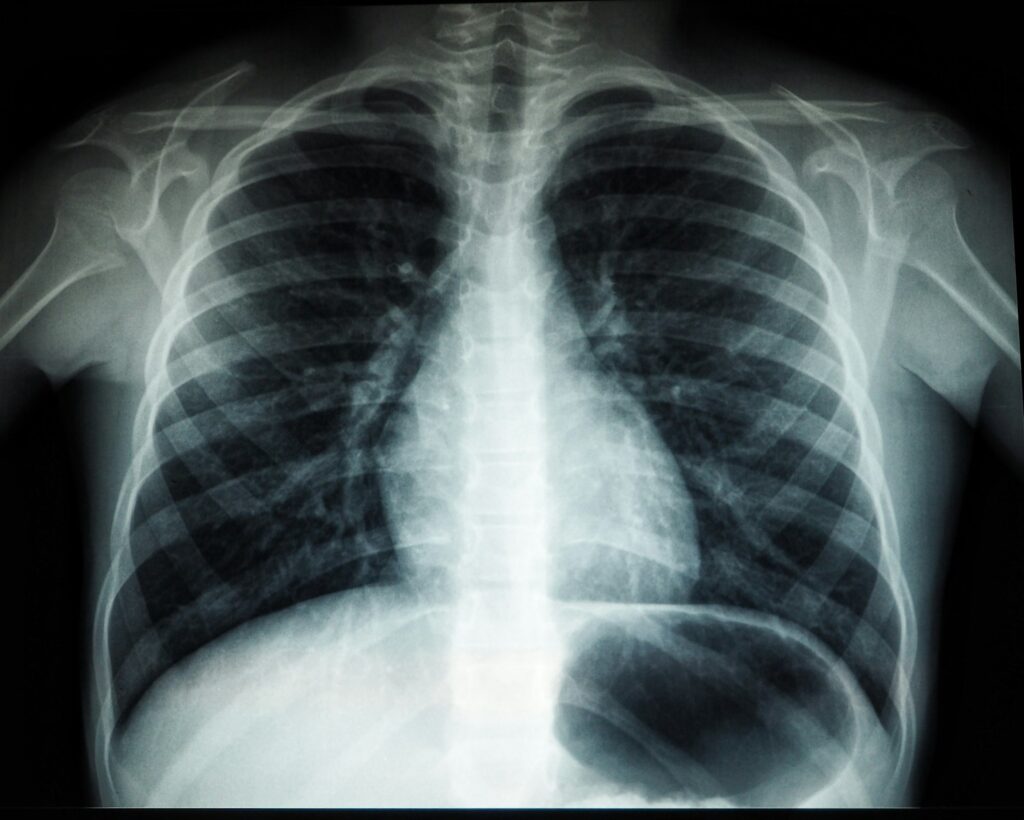

Radiografias (X-ray) e ressonância magnética (RM) são ferramentas úteis, mas cada uma serve a propósitos diferentes. A radiografia mostra principalmente estruturas ósseas, alinhamento e alterações degenerativas, enquanto a RM oferece visão detalhada de discos, nervos, músculos e tecidos moles. Entender essas diferenças ajuda a evitar expectativas incorretas e a conversar com seu profissional de saúde sobre o que realmente é relevante para o seu caso. Lembre-se: imagem não substitui uma avaliação clínica cuidadosa.

A radiografia é útil para confirmar fraturas, avaliar desalinhamentos ou deformidades ósseas, e observar alterações degenerativas que afetam a anatomia da coluna ou das articulações ao redor. Ela é rápida, geralmente disponível e envolve uma dose de radiação que, apesar de mínima, é considerada quando os benefícios superam os riscos. Em quiropraxia, a radiografia pode ajudar a entender a posição das vértebras, o alinhamento da coluna e alterações ósseas que possam influenciar o tratamento conservador.

É importante notar que a radiografia tem limitações. Tecidos moles como discos intervertebrais, ligamentos e nervos não aparecem com muita nitidez, o que significa que achados normais não excluem problemas de disco ou compressão nervosa. Por isso, a decisão de pedir uma radiografia geralmente depende de sinais de alerta, histórico de trauma significativo ou suspeita de condições que afetam o osso ou a articulação. Para conhecer mais sobre como a radiografia funciona e o que ela revela, consulte fontes especializadas de radiologia, como as informações oficiais de radiologia veterinária e humana disponíveis online.